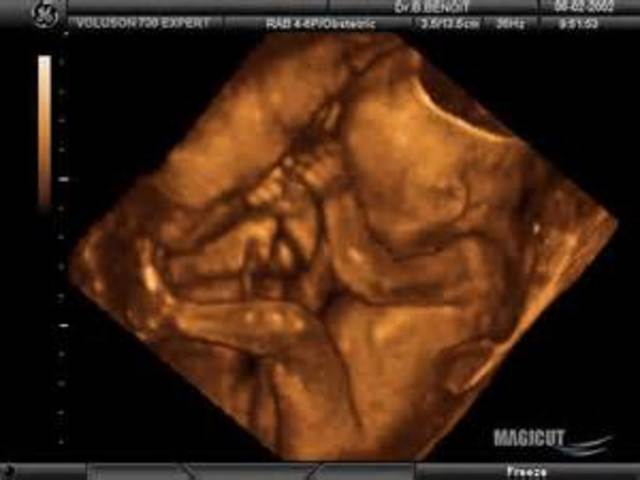

As the placenta continues to grow, the fetus also is growing to about 6.5 inches long and 9 ounces. In an ultrasound, the baby is known for having distinct scalp hair, genitalia, and heart structure.